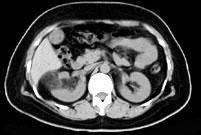

问题 男,55岁,因右腰部不适1 年余,行CT扫描如图所示,下列说法正确的是 ( )

选项 A、考虑为右肾癌 B、考虑为右肾错构瘤 C、其内见低密度脂肪影 D、其边缘清楚,与周围境界清晰 E、右肾中极可见一类圆形肿块影,肿块密度不均

答案 BCDE